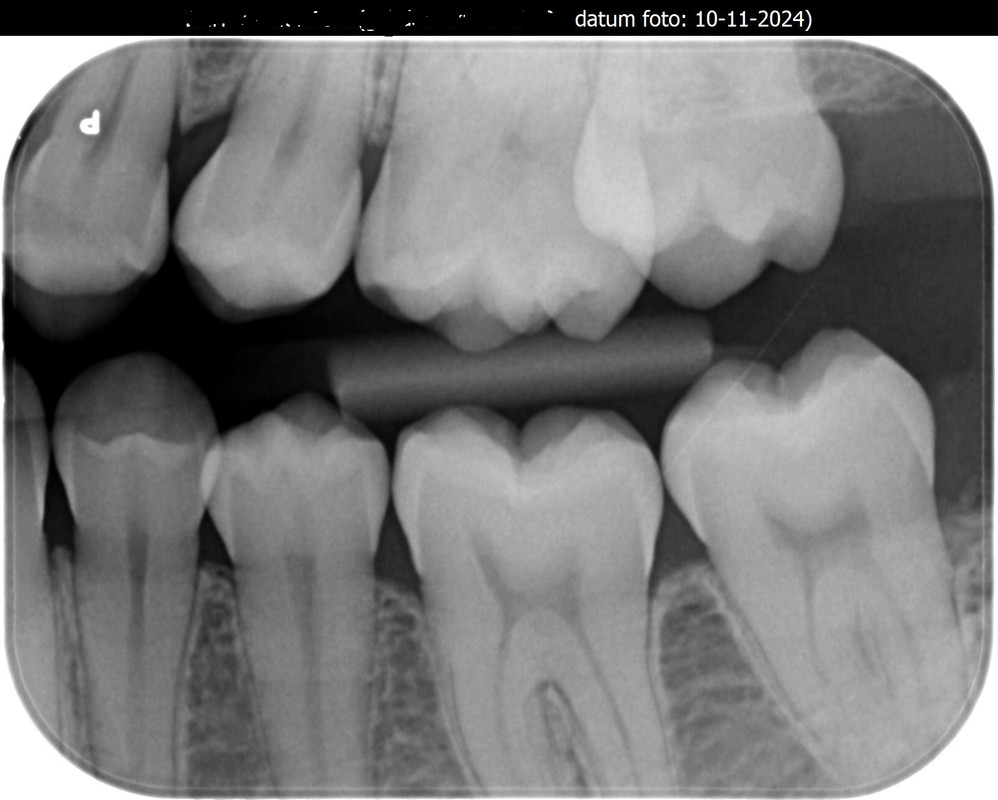

Ik heb de foto bij de tandarts opgevraagd. Wat vinden jullie?[/img]https://i.postimg.cc/8Pg5bcfR/064020-001-20241115.jpg[/img]

[img]https://i.postimg.cc/XvBShKTp/Visi-Quickv12-10-11-2024-1.jpg[/img]

[img]https://i.postimg.cc/XqQzXXTR/Visi-Quickv11-10-11-2024-1.jpg[/img]